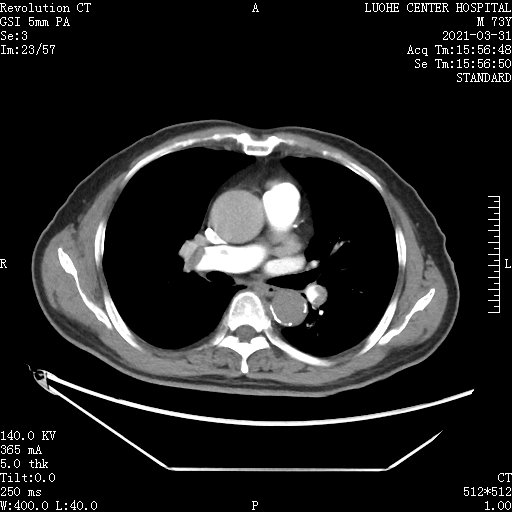

完善肺动脉CTA提示: